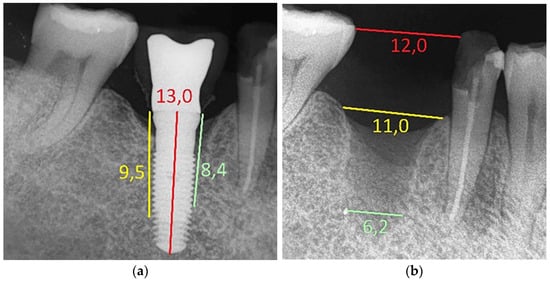

- Bone level changes were evaluated by comparing the measurements at baseline (on the day of prosthesis delivery) with those at follow-up visits. Measurements were obtained with an intraoral radiograph that depicted the vertical distance between the implant shoulder and the most coronal bone contact with the implant surface at mesial and distal sites. All the intraoral radiographs were taken using the parallel technique with an individual tray to ensure reproducibility. Measurements were always performed by the same experienced operator (S.B.) through the software ImageJ version 1.46 (National Institutes of Health, Bethesda, MD, USA), using the known TM implant diameter for calibration. The mesial and distal values were averaged to have a single value per implant.

| 3 | 46 | 8.4 | 9.5 | 10.7 | 5.6 | 25 | 54\53 | 72\67 | 74\72 | 80\82 | 84\83 | |